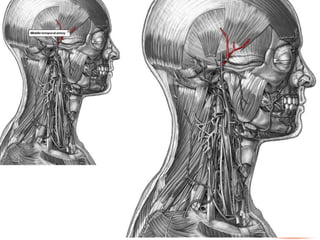

• Se origina en la arteria carótida

común.

• En el niño, es algo más pequeña que

la carótida interna, pero, en el adulto,

los dos vasos son de

aproximadamente el mismo tamaño.

ARTERIA CAROTIDA EXTERNA • Se origina en la arteria carótida común. • En el niño, es algo más pequeña que la carótida interna, pero, en el adulto, los dos vasos son de aproximadamente el mismo tamaño.